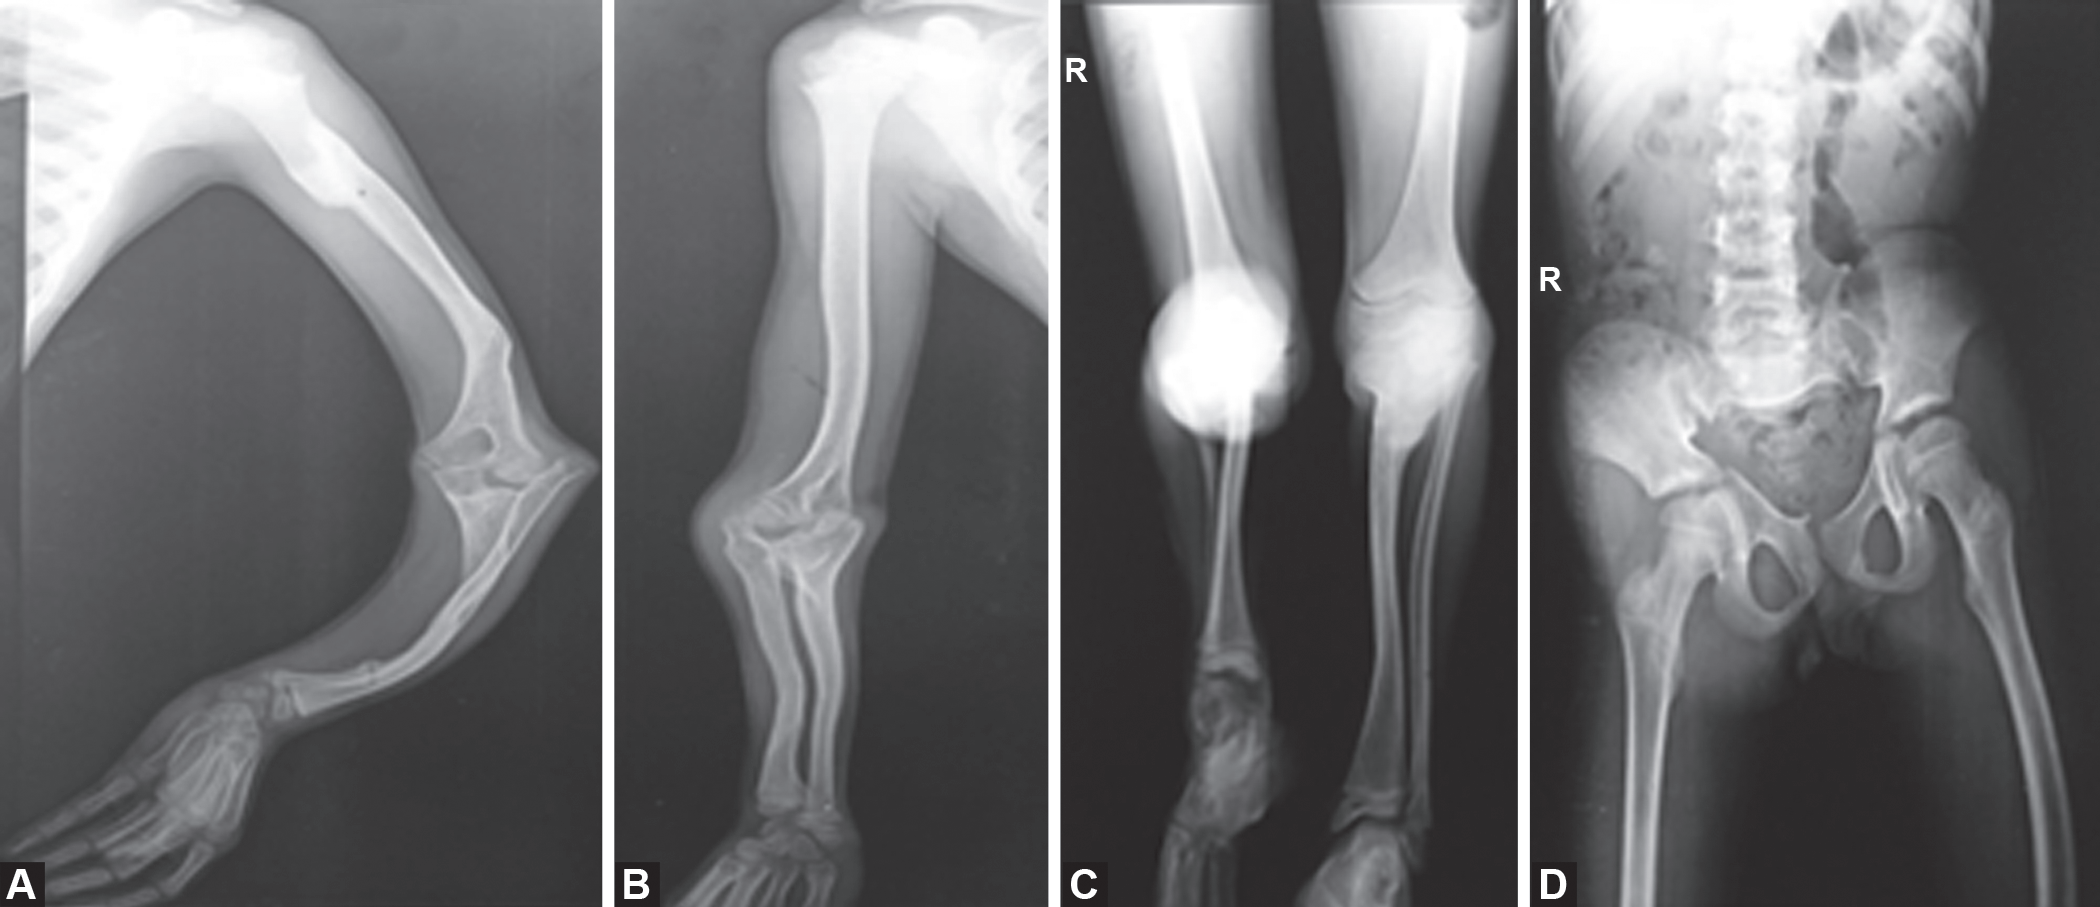

影像学照片

脆骨病的诊断及特点

影像学和分子诊断技术的进步,可以实现在妊娠早期诊断。而轻度的成骨不全症有时直到成年才能被发现以前,大多数病例只能在妊娠中期使用超声(US)检查,若怀疑为成骨不全症,明确诊断需要侵入性基因检测。

脊柱侧凸Cobb角>30、且年龄为11~12岁的0I患者,需要临床随访及定期x线检查,如果侧凸进展明显,则应及时进行矫形手术,并且术后应保持脊柱稳定。成人OI患者常发生听力缺失,起初仅是传导性听力缺失,随着疾病进展,感觉性听力缺失也逐渐出现,因此建议青春期后每3~5年需对0I患者的听力进行监测。针对听力缺失的治疗,疾病开始仅需应用助听器即可达到治疗效果,随着听力缺失进一步加重,患者需行镫骨切除术,其治疗效果较好。